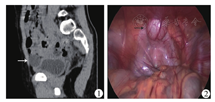

本组除1例为行腹腔镜隐睾手术时偶然发现,余14例均进行了影像学检查(表2)。其中1例为"急腹症",直接进行了全腹部CT平扫;其余13例均首先行B型超声检查,且其中5例进一步行CT或MRI平扫以了解病灶性质及范围(图1)。

患儿术前留置导尿,在全身麻醉下,取平卧位,采用三孔法进行手术。使用5 mm 30°腹腔镜、5 mm或3 mm腹腔镜器械。视野孔置于脐部与剑突连线中点,操作孔位于两侧腹直肌外缘、脐部与视野孔中点水平,气腹压力8~12 mmHg。术中首先分离脐下网膜粘连,确认脐正中韧带及脐尿管囊肿(图2),然后使用电凝钩或超声刀分离脐尿管周围腹膜,游离脐尿管近端至脐部、远端至膀胱上方,分别在分界处结扎后离断。如脐尿管囊肿与膀胱边界不清,则向导尿管内注入生理盐水使膀胱充盈,确定囊肿与膀胱的分界后切除。经5 mm Trocar处取出标本,必要时扩大切口。所有患儿术后均予广谱抗生素预防感染。